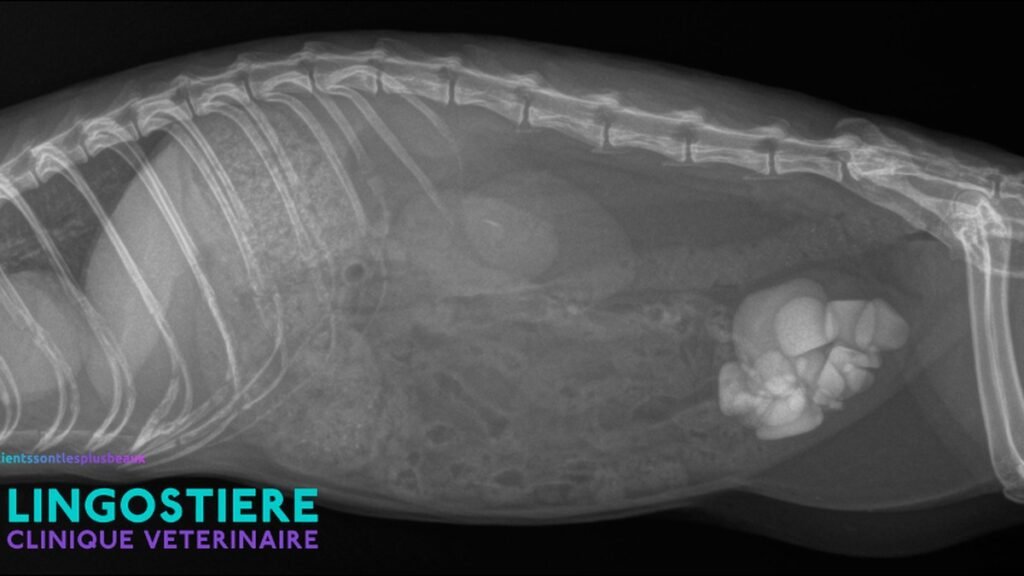

À découvrir : Cas Clinique Furet – Urgence et chirurgie urinaire Drs MARIO & MARTINEZ Calculs de cystine : la